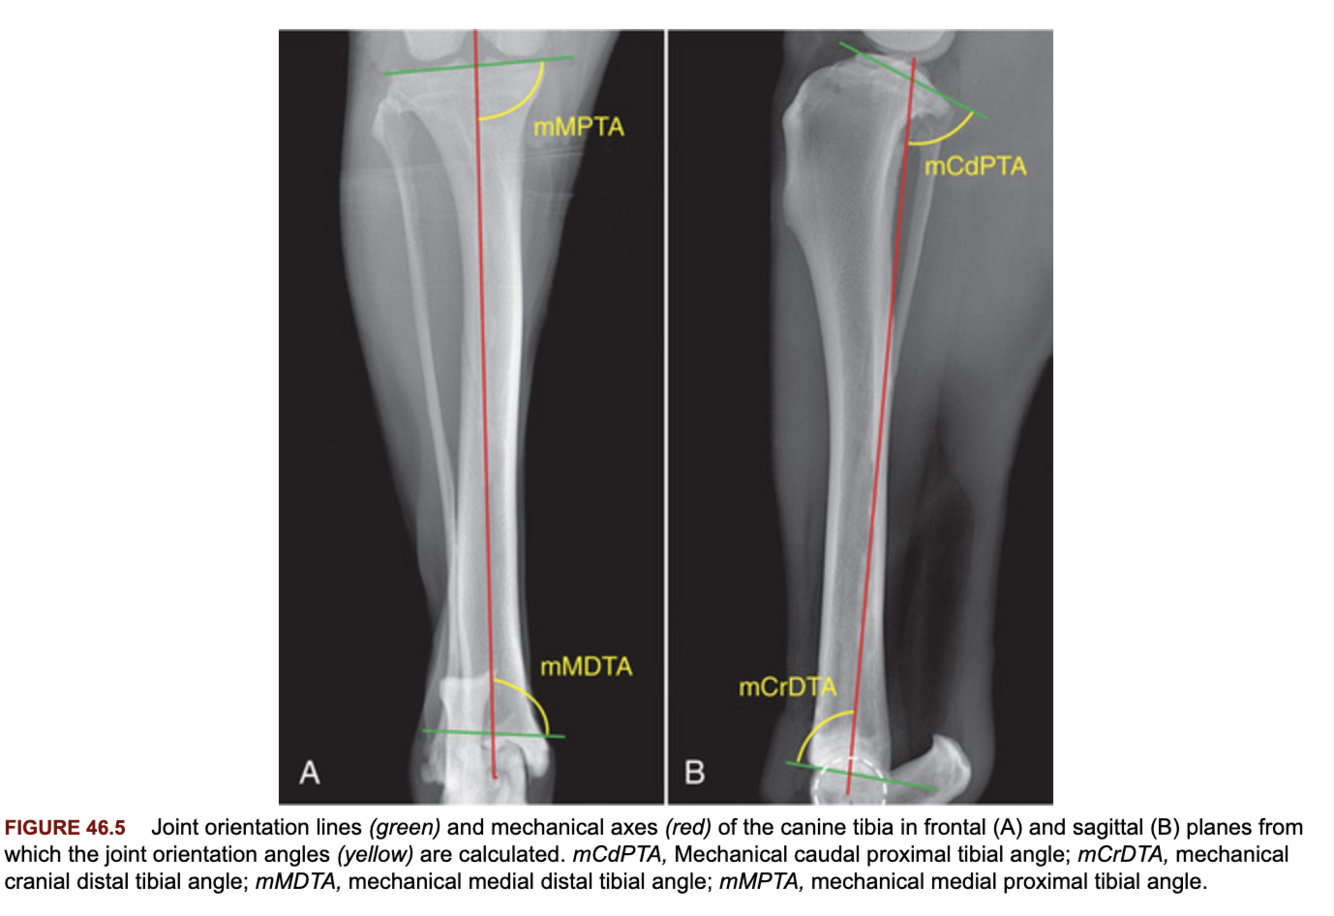

Describe the method of radiographic measurement of the joint orientation lines of the tibia?

A

Frontal: distal points of the subchondral bone concavities proximally, proximal points of the arciform grooves of the cochlear tibiae.

Sagittal: cranial and caudal aspects of the medial tibial condyle proximally, cranial tibial ridge and caudal tibial cochlea distally.

What is the tibial slope as it relates to the joint orientation angle of the tibia?

It is the reciprocal of the mCdPTA (typically around 24-26 degrees).